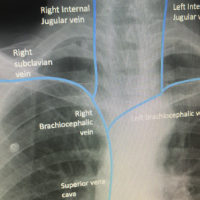

Lines, Tubes and Devices on Chest X-ray

Rapid recognition of incorrect placement of devices, lines, or tubes on chest radiographs is a key skill and vital to ensuring patient safety. This package covers the basics of airway management devices, vascular lines, pleural drains, cardiac conduction devices and nasogastric tubes seen on chest X-rays.